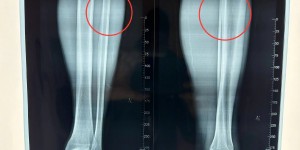

龙八国际3月10日讯 据媒体人李晶报道,国安队长王刚今天经检查后确认骨折。

关于王刚的情况,李晶在社媒透露:“昨天感觉没大事儿。今天拍片子检查,骨折。刚哥,好好休息,早日康复!”

另据博主“埃莱夫赛”透露,王刚将因伤缺席3个月,他在社媒写道:“屋漏偏逢连夜雨!钢铁战士,骨裂,3个月后见!”